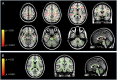

Methods: Among 550 people with a tentative diagnosis of MS or neuromyelitis optica spectrum disorder (NMOSD), we selected patients, who met the 2010 McDonald diagnosis criteria for MS, but did not show abnormal findings on conventional brain and spinal cord MRI. After evaluating their clinical data, we analyzed fractional anisotropy (FA) values in the brain white matter on diffusion tensor MRIs and the frequencies of B-cell subsets in the peripheral blood in the corresponding cases as compared to healthy controls.

Results: Eleven patients (age: 41.1 ± 8.0 years, 9 women and 2 men) met the selection criteria. They were functionally disabled, with a median expanded disability status scale score of 6.0 (2.0-8.0). CSF oligoclonal bands were negative in all cases. IV methylprednisolone and plasmapheresis (PP) were found to be efficacious. Diffusion tensor MRI analysis revealed extensive white matter abnormalities characterized by significantly decreased FA values. The frequency of plasmablasts in the peripheral blood was significantly increased in these patients similar to NMOSD.

Conclusions: The neurologic disabilities in these patients could be ascribed to brain white matter damage, as revealed by MRI analysis, whereas the efficacy of PP and B-cell abnormalities in the patients suggested an autoimmune-mediated pathogenesis. In the differential diagnosis of MS, we propose that this condition be referred to as, "Normal-appearing Imaging-associated, Neuroimmunologically Justified, Autoimmune encephalomyelitis."